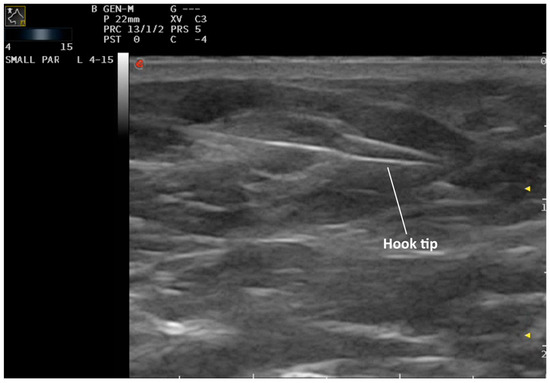

Ultrasound-Guided Hook-Wire Localization for Surgical Excision of Non-Palpable Superficial Inguinal Lymph Nodes in Dogs: A Pilot Study

2. Materials and Methods